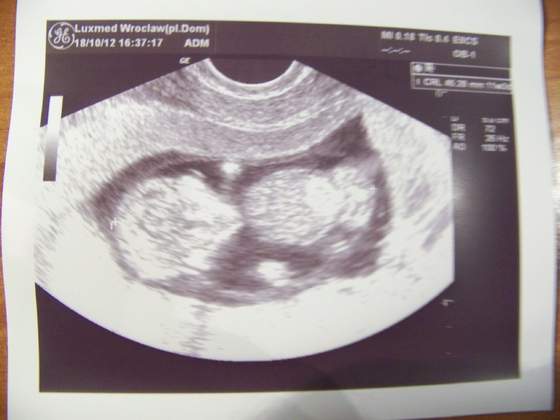

Ja już po wizycie, dzidzia rośnie jak powinna i jest wszystko w porządku. Ułożyła się tak, że doktórka nic nie dostrzegła czy coś tam dynda czy nie

Termin z USG to 1.05.2013 czyli ledwo się łapię na majóweczkę.

Dołączam zdjęcie mojego 4,5 cm szczęścia.